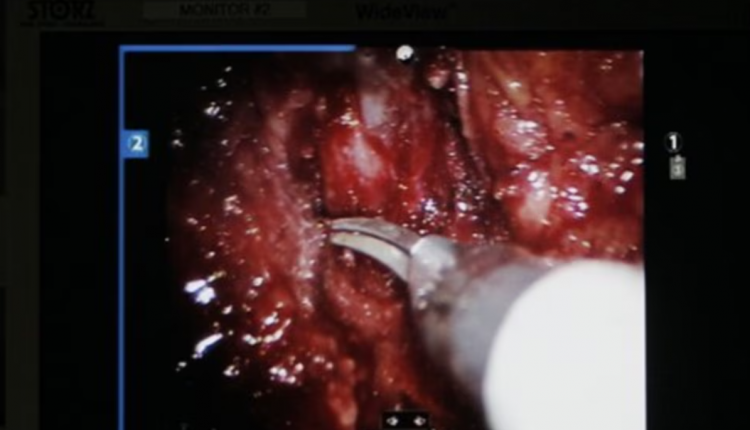

Por, krahë robotikë kryejnë një operacion delikat në rrugët urinare të pacientit.

Krahët robotikë bëjnë pjesën më të madhe të punës, ndërsa kirurgu kryesor përdor leva për t’i kontrolluar dhe drejtuar ato.

Ndërsa krahët robotikë të përdorur në këtë procedurë kanë një gamë lëvizjeje të tillë që bën të mundur që instrumente kirurgjikale mjaft të vogla të kryejnë operacione të ndërlikuara te fëmijët.

Pajisja e ndihmuar nga roboti, e zhvilluar nga CMR Surgical Ltd me bazë në Kembrixh, synon të arrijë një saktësi që njeriu nuk e arrin dot, nëpërmjet përdorimit të instrumenteve të vogla kirurgjikale, kontrollit të robotit, si dhe një ekrani të zmadhuar me rezolucion të lartë.